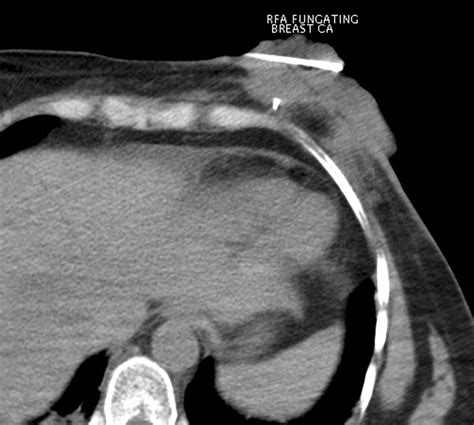

Fungating Breast Cancer

Receiving a diagnosis of fungating breast cancer is an incredibly distressing experience, often accompanied by complex physical and emotional challenges. This condition, medically referred to as malignant wound, ulcerating breast cancer, or fungating carcinoma, occurs when a tumor grows through the skin, creating an open, often non-healing wound. Understanding what this diagnosis means, how it develops, and the palliative care strategies available is essential for patients, caregivers, and families navigating this difficult journey. While the diagnosis is advanced, modern medical management focuses heavily on symptom control, comfort, and maintaining quality of life.

Fungating breast cancer is not a specific type of cancer itself, but rather a clinical presentation that can occur with various types of breast malignancy. It develops when a primary tumor or a metastatic lesion in the breast grows outward, invading the skin barrier. As the tumor increases in size, it outgrows its blood supply, leading to tissue necrosis—the death of cells—which creates the characteristic open, fungating wound.